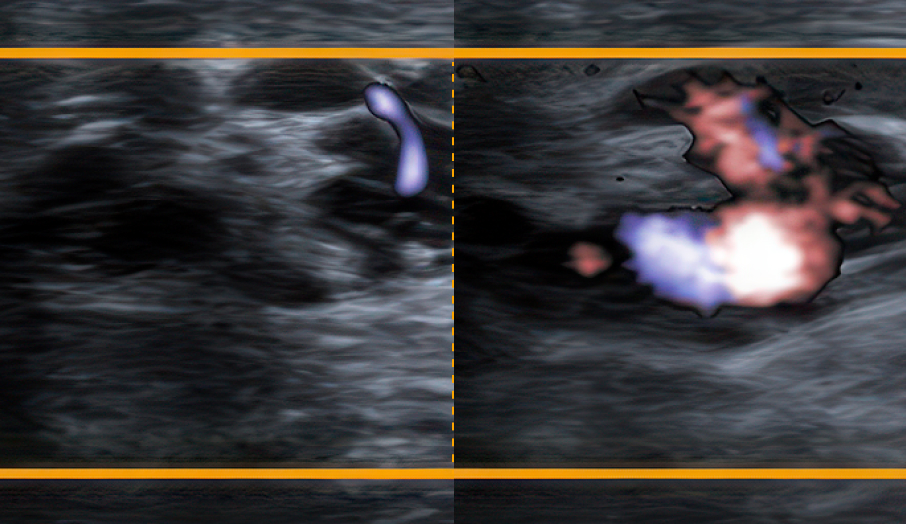

정맥혈이 고여

음낭 내부의 온도를 높임